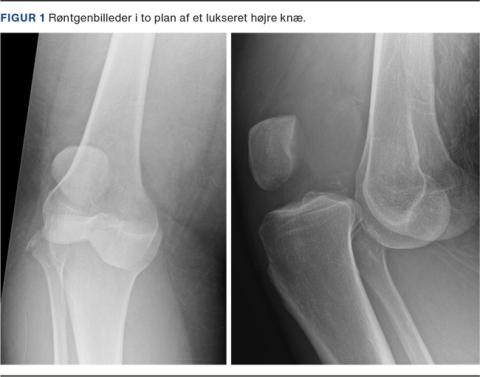

Traumatisk knæluksation defineres som en komplet dislokation af det tibiofemorale led (se Figur 1) og sekundært som ruptur af minimum to af de fire vigtigste stabiliserende ligamenter i knæleddet [2]. Luksation kan være en følge af både høj- og lavenergitraumer og ses med næsten ligelig fordeling. Trafikulykker er hyppigste højenergitraume, og sportsaktivitet er hyppigste lavenergitraume [3]. Gennemsnitsalderen er 35 år med faldende incidens med alderen [4]. Overvægt er enkeltstående risikofaktor for traumatisk knæluksation, eksempelvis ved et simpelt vrid i knæleddet. Der er i litteraturen beskrevet en stigende incidens i denne patientgruppe som følge af lavenergitraumer og med samme grad af kar- og nerveskader [5].

Den akutte vurdering af et lukseret knæ indbefatter anamnese med information om skadesmekanisme efterfulgt af klinisk vurdering og diagnostik med initial fokus på reposition og neurovaskulær status. Det lukserede knæ vil ofte præsentere sig med udtalt deformation. Ved åbenlyst lukseret knæled udføres umiddelbart lukket reposition for at undgå yderligere skader på kar, nerver og bløddele. I tvivlstilfælde forudgået af røntgenundersøgelse. Reposition kan udføres såvel i skadestuen som på operationsstuen.